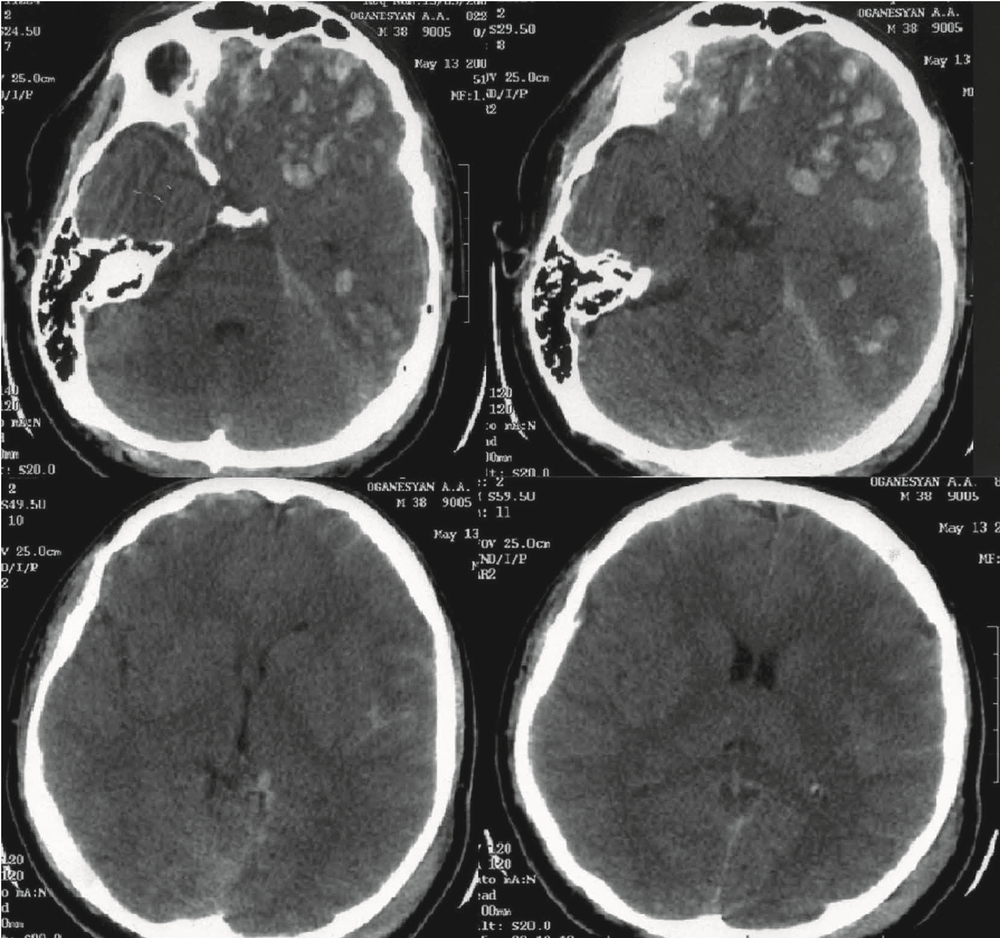

Вторые сутки. Пострадавший был переведен в НИИ нейрохирургии. Диагноз: тяжелая открытая ЧМТ. Ушиб головного мозга тяжелой степени с формированием множественных очагов ушиба (33 вида) в лобных долях с двух сторон, левой височной доле. Линейный перелом затылочной кости слева с переходом на основание. Травматическое САК. На К.Т. сохраняется прежняя картина (рис. 1).